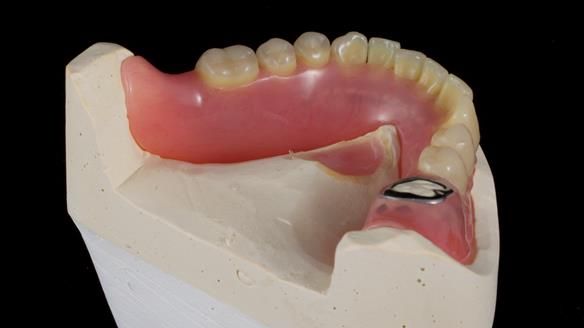

However, once Rowan and I reviewed the remaining metal crown on tooth 46, we realised it would make an ideal abutment for a gasket denture. By reshaping the lingual surface of the crown, we created an excellent gasket seal.

This approach worked far better than the proposed ring-clasp design - improving retention, comfort, and aesthetics while keeping the design clean and simple.

- The gasket seal around 46 was made using retention.sil 200, producing a precise, cushioned fit.